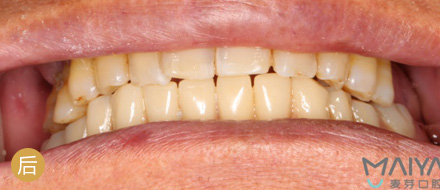

• all-on-4半口种植

4颗牙钉恢复半口